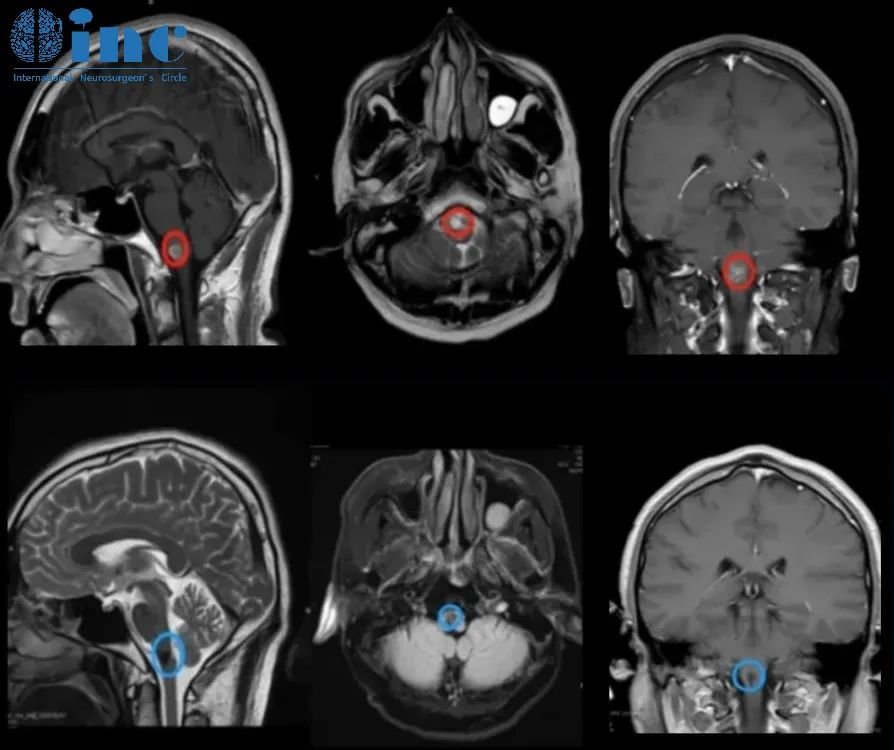

◉患者情况:2022 年 9 月 8 日19岁的阿朔出现无明显诱因的头痛和晕胀感,从颞侧到枕后。10 月 10 日于苏州独墅湖医院行颅脑核磁提示延髓异常信号,考虑海绵状血管瘤。

◉治疗过程:在2022中德学术交流-INC巴特朗菲教授示范国际疑难脑瘤手术直播,INC旗下的国际神经外科教授德国巴特朗菲教授受邀围绕“脑干海绵状血管瘤的手术”做课程演讲,并进行线上线下延髓手术示范直播。手术顺利全切阿朔延髓海绵状血管瘤,直播观看人次达7000多,除了神经外科医生观看外,还有即将接受教授手术的患者家属共同观看。

◉术后情况:术后1天巴教授ICU查房,阿朔意识清楚、对答如流、四肢活动灵活;术后5天,可正常站立、行走;术后8天,阿朔状态很好,正逐步回归正常生活。术后一个月,阿朔回到大学校园,回归正常的学习和生活。术后3个月,阿朔还接受了INC专访,交流自己的治疗经历,希望能够帮到更多的人。